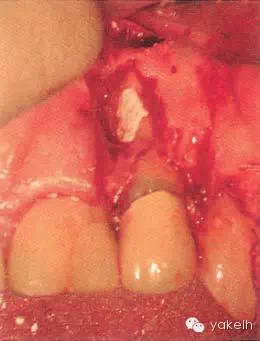

¤¤口外檢查可見(jiàn)顳下頜關(guān)節(jié)處輕微捻發(fā)音,開(kāi)口度、開(kāi)口型正常,無(wú)疼痛,未見(jiàn)其他異常??趦?nèi)檢查可見(jiàn)牙列中有部分良好的修復(fù)體,無(wú)齲壞;局部牙齦炎,探診出血,牙周探診深度不超過(guò)2mm。22唇側(cè)牙槽黏膜可見(jiàn)竇道(圖5.4.1a),輕微叩痛,竇道區(qū)捫痛,根尖X線片顯示牙根中部透射影,疑為樁穿孔(圖5.4.1b)。左上頜中切牙(21)和左上頜尖牙(23)對(duì)EPT和冷測(cè)試反應(yīng)正常。

圖 5.4.1(a)22唇側(cè)牙槽黏膜略腫。